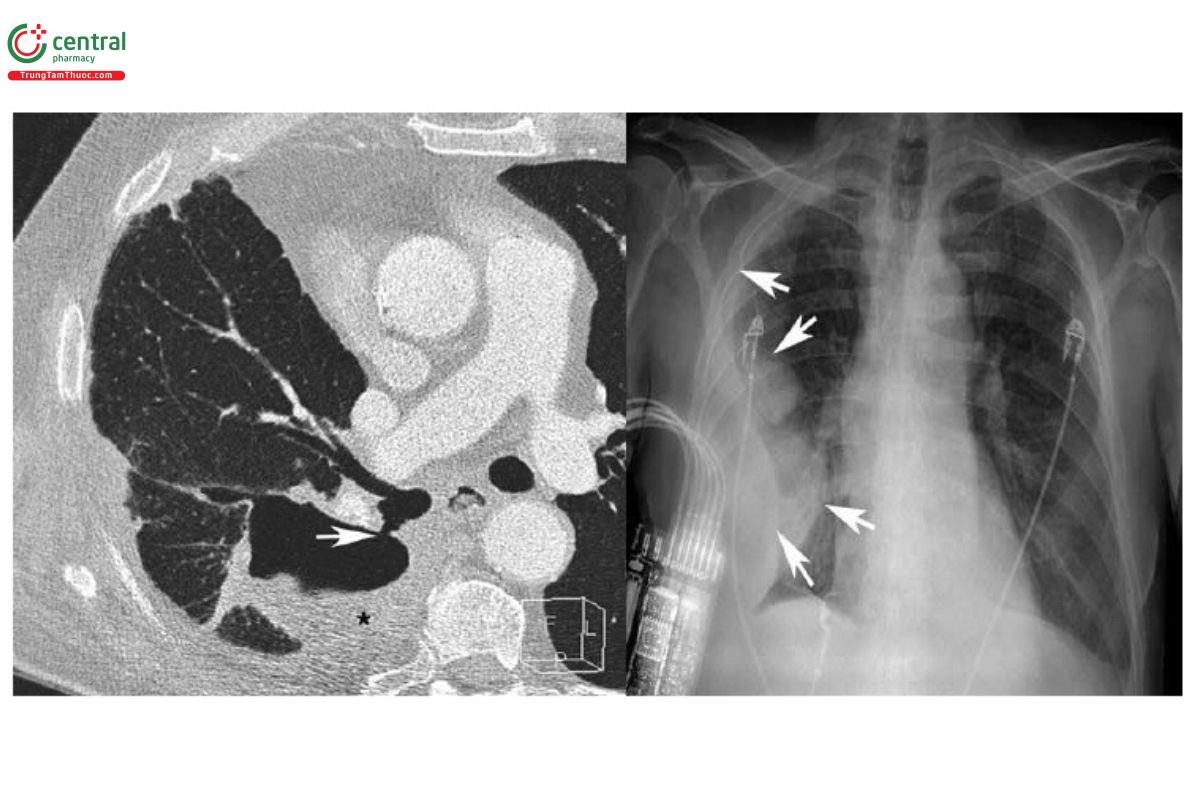

Đánh giá các biến chứng và chẩn đoán phân biệt viêm phổi: CT có giá trị xác định các biến chứng ở phổi và chẩn đoán phân biệt viêm phổi; hướng dẫn lựa chọn vị trí sinh thiết phổi xuyên phế quản hoặc sinh thiết qua da và dẫn lưu áp xe hoặc dịch màng phổi ở bệnh nhân viêm phổi. Hình ảnh rò phế quản - màng phổi (Bronchopleural Fistula - BPF) trên CT biểu hiện bằng đường dẫn trực tiếp giữa cây phế quản hoặc nhu mô phổi và khoang màng phổi. CT giúp đánh giá sự hiện diện, vị trí và kích thước của rò phế quản - màng phổi [6,20]